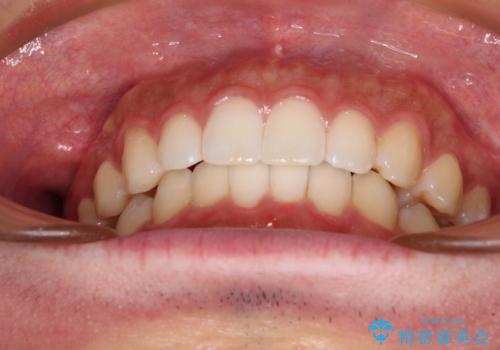

前歯のデコボコと突出感 インビザラインにて矯正治療

ご自宅と職場がともに遠方であったため、治療期間は長くなりましたが、患者様も我々も期待して以上に口元の突出感を改善することができました。

左上の小臼歯は捻転が強く、あえて180逆向きの状態で終了させる治療計画としました。